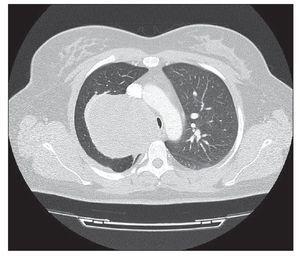

Mujer de 35 años, sin antecedentes de interés, que presentaba clínica progresiva de 5 meses de evolución de ptosis palpebral y dolor pleurítico derecho. A la exploración física había ptosis palpebral derecha leve de 2 mm respecto al párpado contralateral e hipoventilación de hemitórax derecho. Realizamos radiografía torácica posteroanterior que mostraba una masa en ápex derecho, por lo que completamos el estudio mediante tomografía computarizada (TC) torácica, la cual mostraba una masa sólida de contorno redondeado y bien definido, de 85 ´ 84 mm de diámetros transversales y 87 mm de diámetro sagital, paravertebral derecha desde D1 (vértebra dorsal) hasta D5-D6, con prolongación hacia el agujero de conjunción de D1-D2 sin invadirlo. La masa desplazaba la tráquea hacia la izquierda, disminuyendo su luz, con diámetro transversal de esta en la parte más estrecha de 6 mm y el anteroposterior de 15 mm (fig. 1), siendo por tanto el diagnóstico más probable un tumor de origen neurogénico. Ante estos hallazgos, realizamos biopsia transtorácica que nos dio un diagnóstico anatomopatológico (AP) compatible con neurofibroma. Se procedió a la exéresis del tumor mediante toracotomía posterolateral derecha. Accedimos a la cavidad torácica y hallamos masa tumoral extrapleural adherida a zona apicoposterior (fig. 2) y ápex pulmonar, sin invasión de estructuras adyacentes. Se liberó tanto de la pleura parietal como del ápex pulmonar, localizando el del pedículo a nivel del 2.º y 3.º espacios intercostales derechos, sin invasión del cuerpo vertebral ni agujero de conjunción, ligadura de este, ni exéresis de la tumoración. El postoperatorio fue favorable y la paciente fue dada de alta 3 días después de la intervención. El diagnóstico AP definitivo fue de neurofibroma.

Figura 1 Masa sólida de contorno bien definido, de 85 ´ 84 mm de diámetros.

Radiológicamente, en la TC de tórax, se presentan como lesiones de baja densidad, masas homogéneas de forma oval y márgenes bien definidos. La apariencia infiltrativa, la presencia de una lesión osteolítica irregular o el aspecto heterogéneo de la lesión son características propias de malignidad.

La imagen que nos proporcionó la TC torácica descartó la afectación del agujero de conjunción y componente intraespinal de la tumoración.